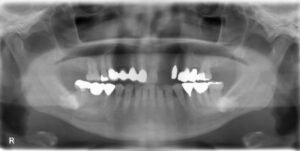

上下5本欠損症例

BEFORE AFTER 62歳女性/上下5本欠損/インプラント埋込手術 【治療内容】 欠損歯が多いため、お食事が取りに…